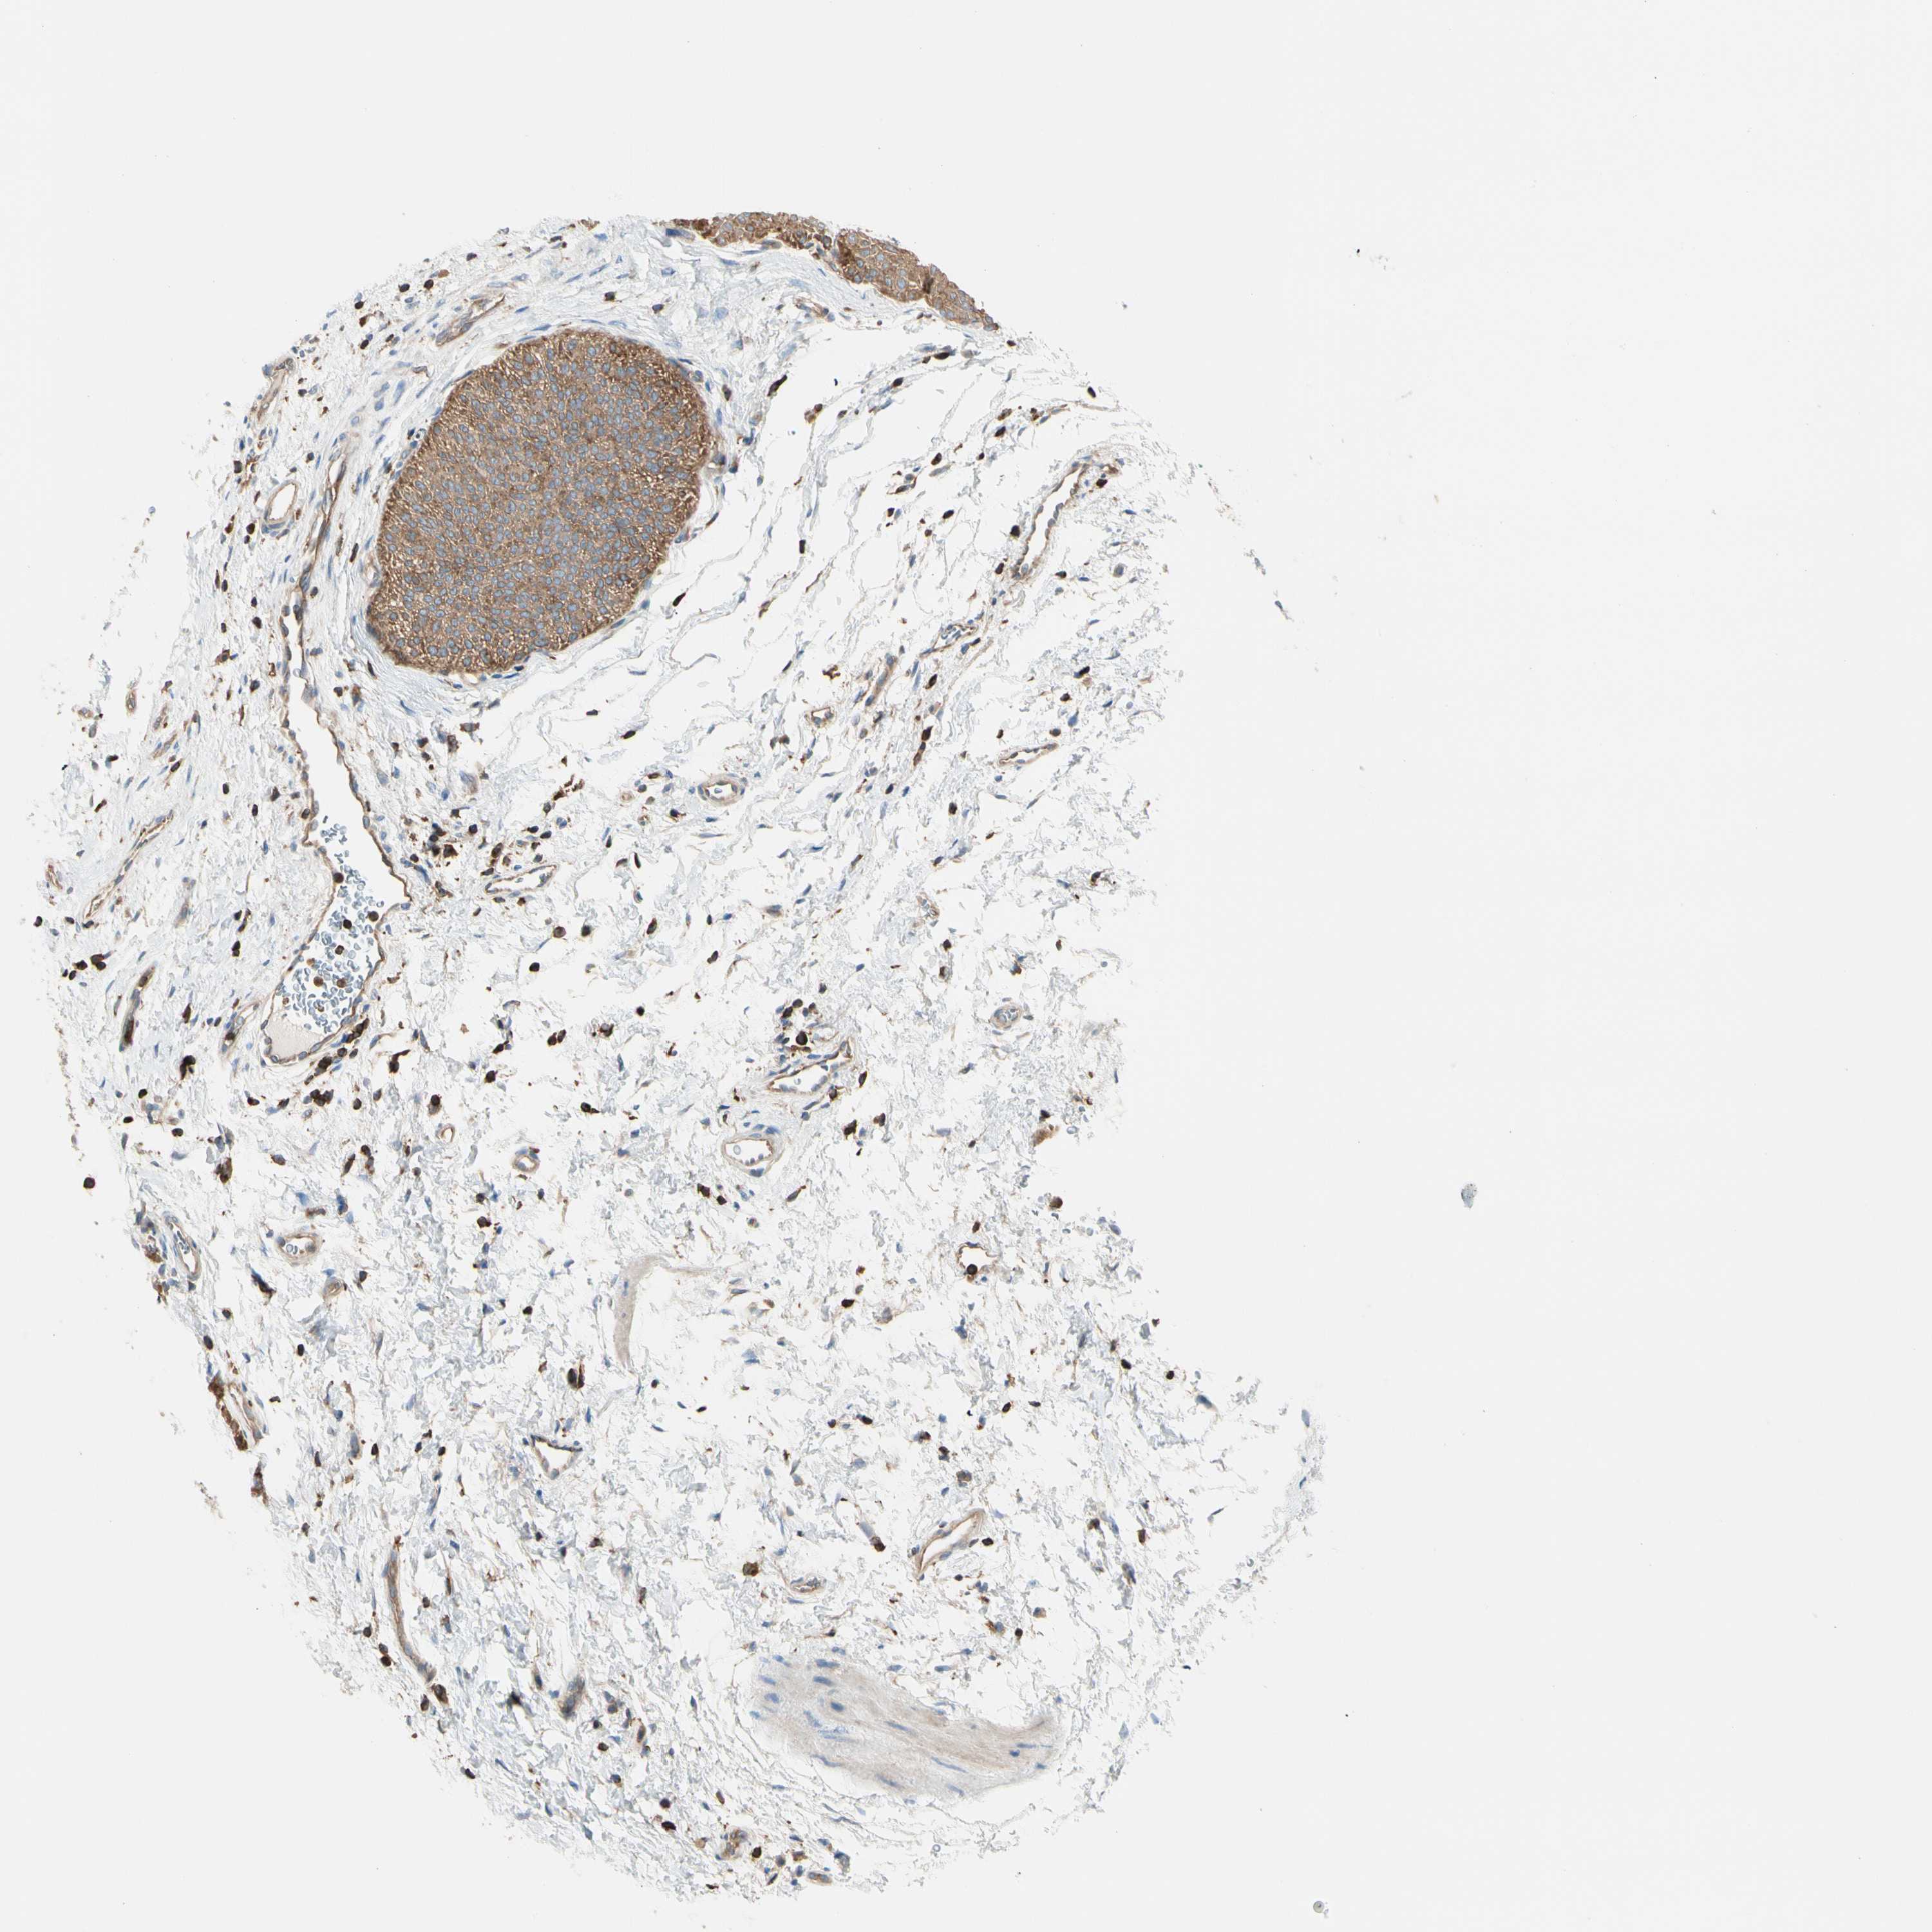

UROTHELIAL CANCER - Protein expressioni

A mouse-over function shows sample information and annotation data. Click on an image to view it in a full screen mode. Samples can be filtered based on level of antibody staining by selecting one or several of the following categories: high, medium, low and not detected. The assay and annotation is described here.

Antibody stainingi

Antibody staining in the annotated cell types in the current human tissue is reported as not detected, low, medium, or high, based on conventional immunohistochemistry profiling in selected tissues. This score is based on the combination of the staining intensity and fraction of stained cells.

Each image is clickable and will lead to virtual microscopy that enables deeper exploration of all samples and also displays staining intensity scores, fraction scores and subcellular localization as well as patient and tissue information for each sample.

Antibody HPA007470

Staining

High

Medium

Low

Not detected

Intensity

Strong

Moderate

Weak

Negative

Quantity

>75%

75%-25%

<25%

None

Location

Nuclear

Cytoplasmic/membranous

Cytoplasmic/membranous,nuclear

Urothelial carcinoma, Low grade

Urothelial carcinoma, High grade